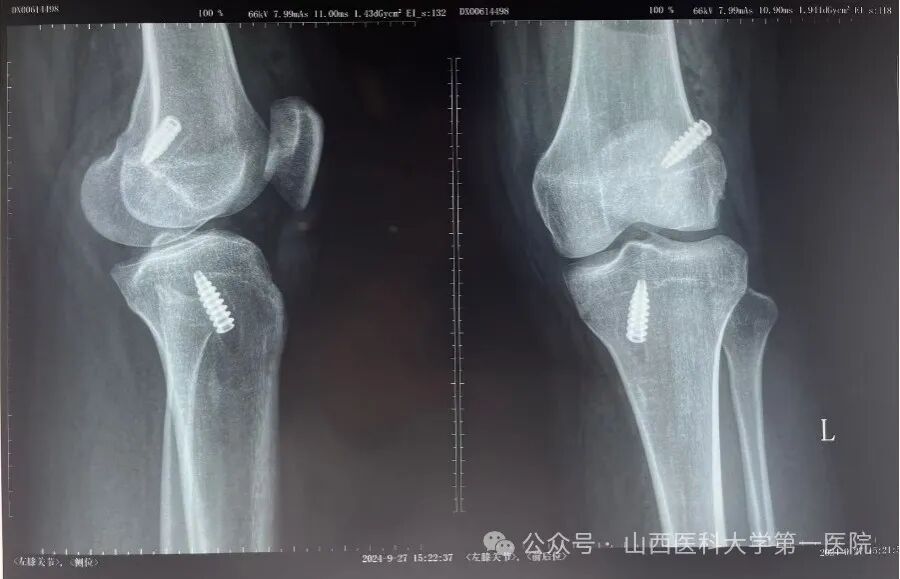

(术后复查X线片显示金属挤压钉位置)